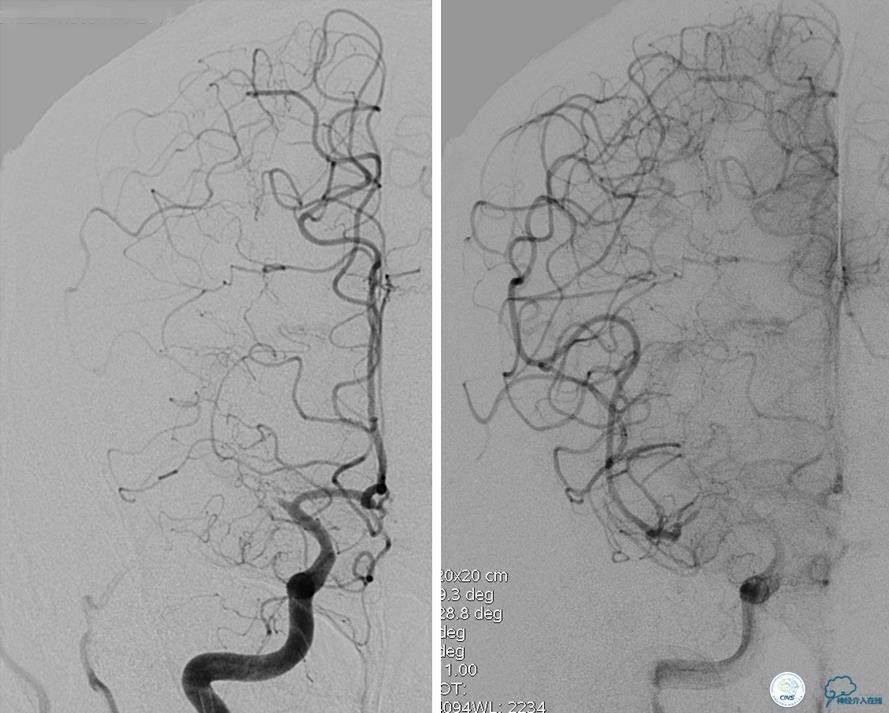

左侧颈内动脉末端闭塞,末端圆钝且有一定成角,开通难度较大,多次尝试导丝才成功穿过闭塞段。

开通效果很满意,术后症状明显恢复。